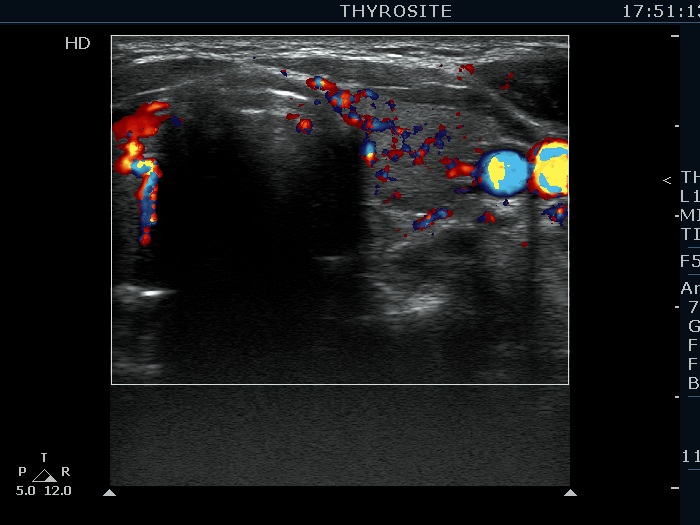

Intranodular hyperechogenic figures - case 1730 (ultrasonographic picture 6)

Left lobe, transverse view, color Doppler mode. The vascularization is increased.